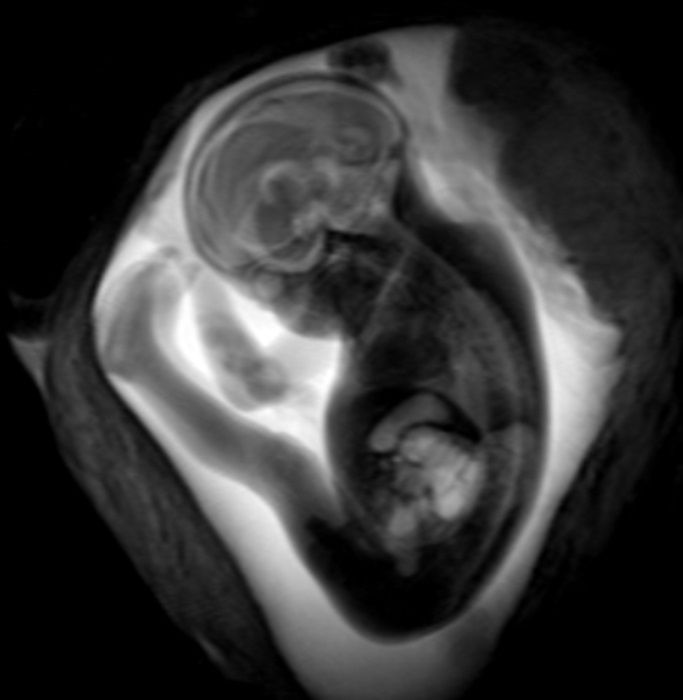

Stöcklein y sus colegas utilizaron la resonancia magnética fetal para estudiar a 33 pacientes con infección por Covid-19 durante el embarazo. Las pacientes llevaban de media 28 semanas de embarazo y el inicio de los síntomas ocurrió tras poco más de 18 semanas de gestación. Los síntomas maternos más comunes fueron pérdida o reducción del sentido del olfato y el gusto, tos seca, fiebre y dificultad para respirar.

Dos radiólogos con varios años de experiencia en resonancia magnética fetal evaluaron las exploraciones. Encontraron que el desarrollo del cerebro en las áreas evaluadas era apropiado para la edad en todos los fetos. No hubo hallazgos indicativos de infección del cerebro fetal.